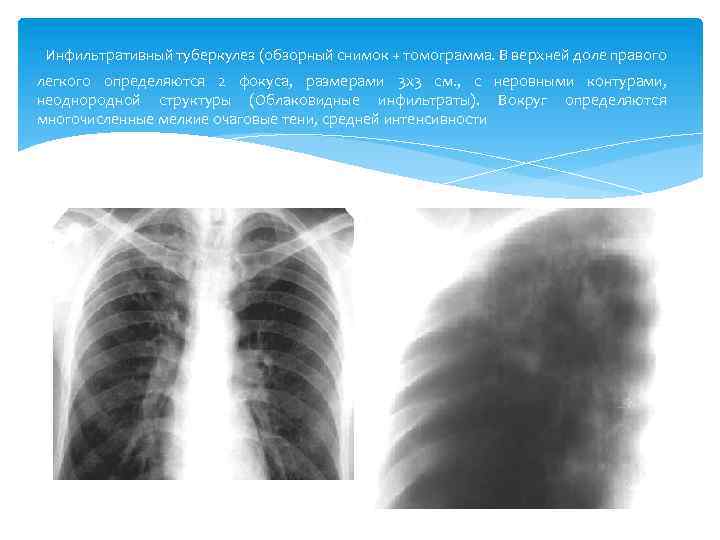

Очаговый и инфильтративный туберкулез презентация - 94 фото